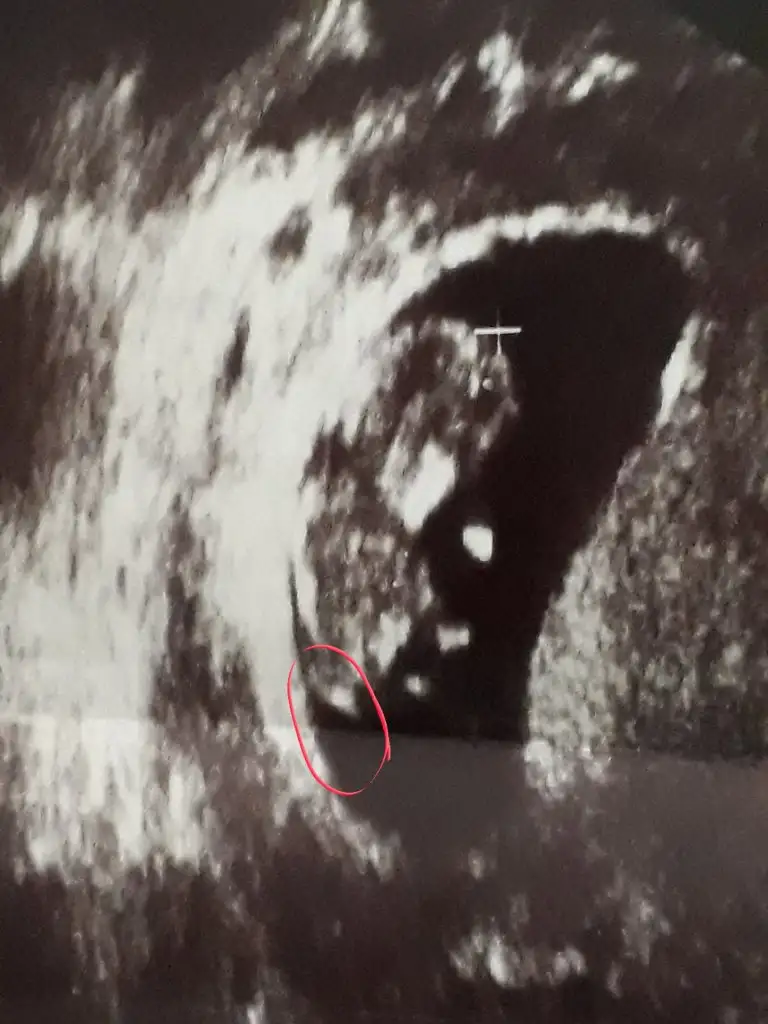

Ikram simdi gordum bu msjini ben bu isaretlediklerimi nub saniyorum kiz hala cozememisim desene nub degil bunlar galiba birde zaten birinde bana gore dik digerinde paralel sanki terzi misali kendi sokugumu dikemiyorum aklim erkekte ya her cikintiyi pipi saniyorum galibaSen daha iyi görüyorsun USG yi resim net değil sen ne diyorsunbebisine

Yok değil nub hiç belli değil canimIkram simdi gordum bu msjini ben bu isaretlediklerimi nub saniyorum kiz hala cozememisim desene nub degil bunlar galiba birde zaten birinde bana gore dik digerinde paralel sanki terzi misali kendi sokugumu dikemiyorum aklim erkekte ya her cikintiyi pipi saniyorum galiba

11 12 13 haftalar olmalı sanki erkek gibi geldi ama istediğim haftalara bakıyorumtutmaya bilir

Erkek gibiHa pardon. Simdi yolluyorum. Bu resim 5 agustosun. 6 mayis son adetim, yani resimde 13.0 haftalik degilmi?

Erkek gibi